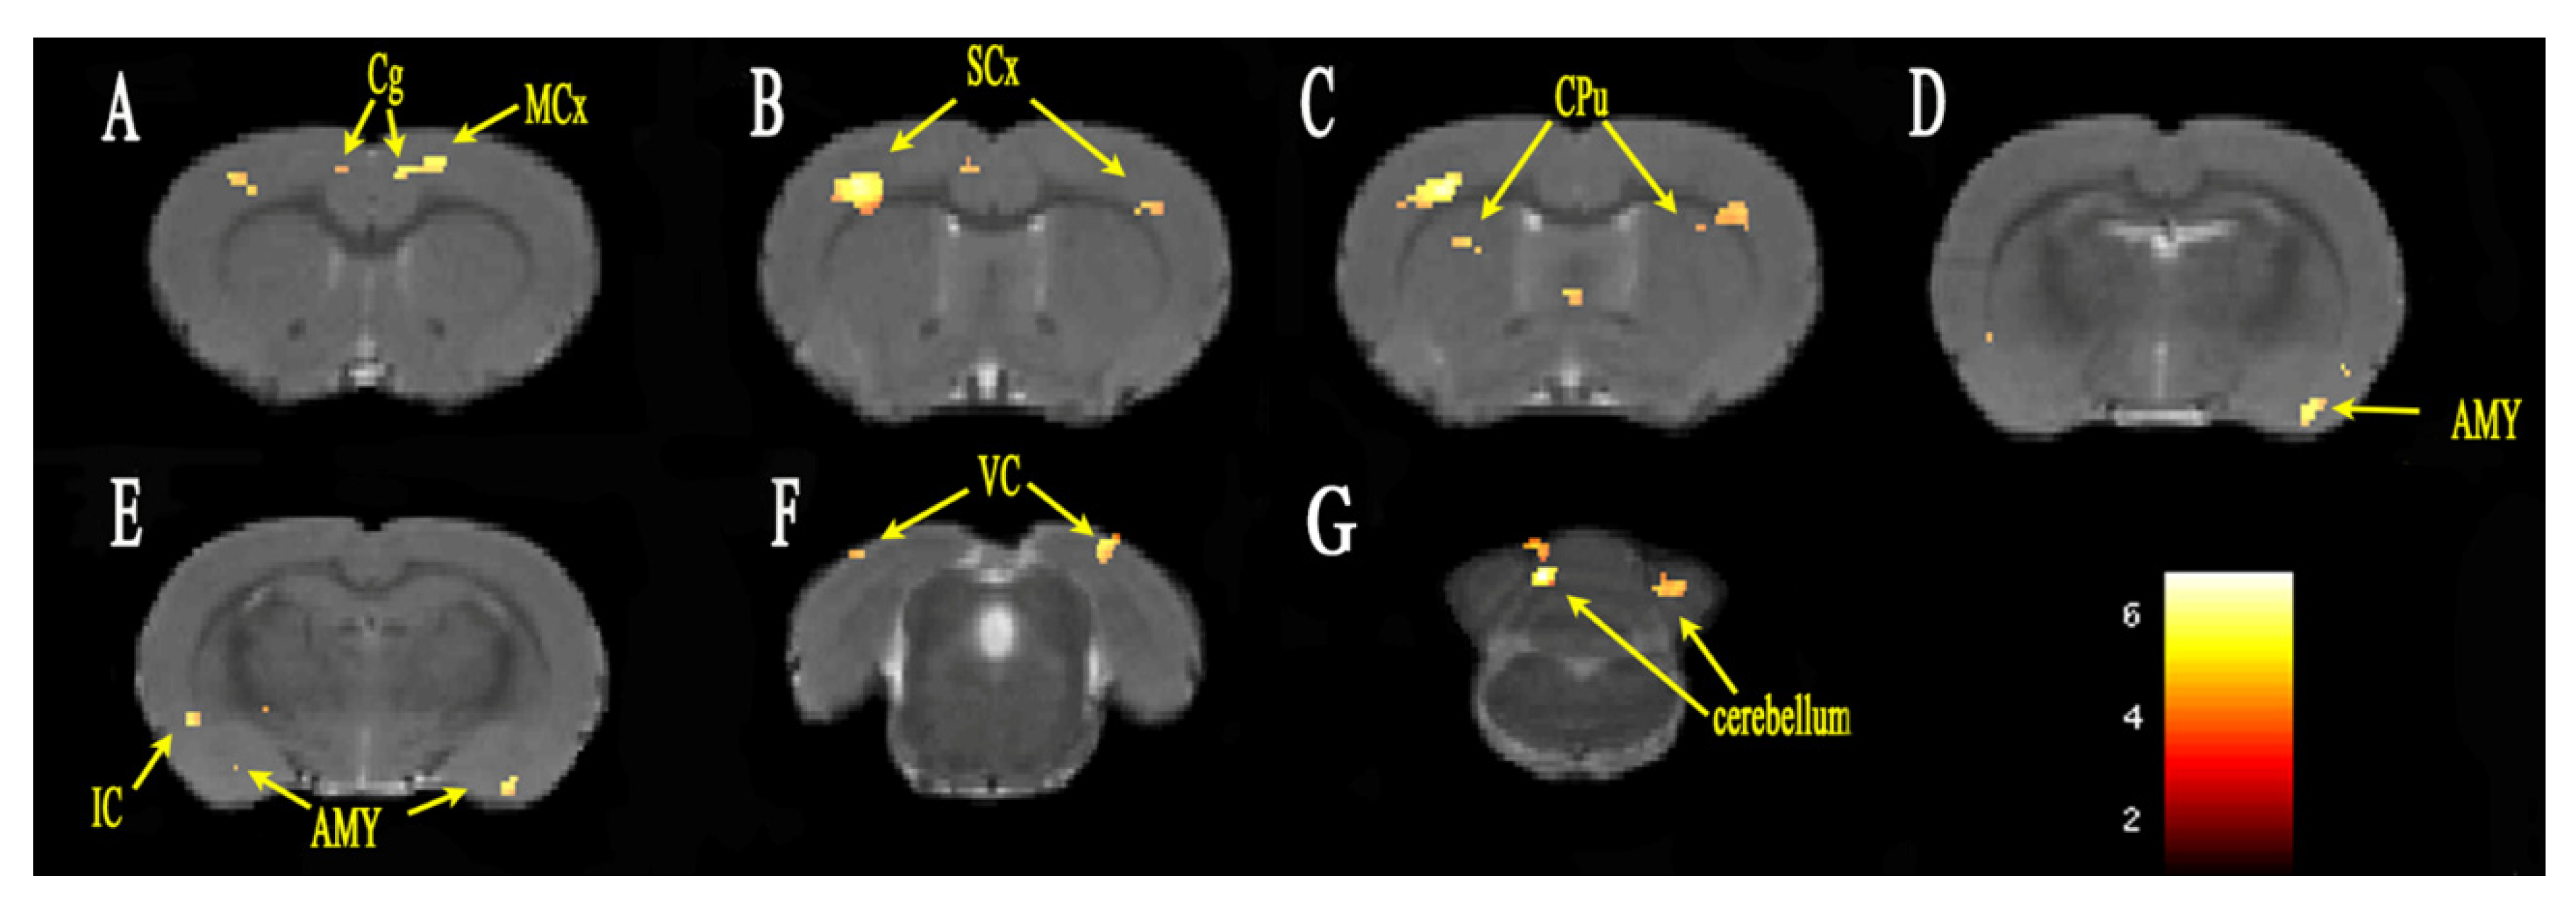

3.2. Functional Connectivity Analysis

| L cingulate gyrus | 87 | 5.037 | 0.4984 | 1.4022 | 1.8021 |

| R cingulate gyrus | 93 | 4.029 | −0.5641 | 1.3830 | 1.3221 |

| L motor cortex | 128 | 5.120 | 1.4339 | 1.1642 | 1.8021 |

| R motor cortex | 31 | 4.065 | −3.6445 | 1.1627 | 1.8021 |

| L sensory cortex | 333 | 5.021 | 4.6644 | 3.8351 | 0.1221 |

| R sensory cortex | 964 | 6.204 | −3.8953 | 1.8379 | 0.6021 |

| L amygdaloid body | 176 | 5.107 | 4.1497 | 8.8969 | −1.3179 |

| R amygdaloid body | 86 | 4.628 | −5.7135 | 9.3718 | −3.2379 |

| L striatum | 97 | 3.972 | 2.6994 | 7.3334 | −2.7579 |

| R striatum | 174 | 4.562 | −3.0901 | 3.6578 | 0.3621 |

| L poaterior lobe of cerebellum | 251 | 5.621 | 3.2290 | 1.9082 | −12.1179 |

| R poaterior lobe of cerebellum | 217 | 6.825 | −1.1515 | 3.3053 | −14.2279 |

| L visual cortex | 547 | 4.854 | 3.8444 | 1.1680 | −8.2779 |

| R visual cortex | 298 | 5.059 | −4.8357 | 1.2926 | −8.7579 |

| R insular cortex | 59 | 4.444 | −5.8636 | 6.3370 | −2.0379 |